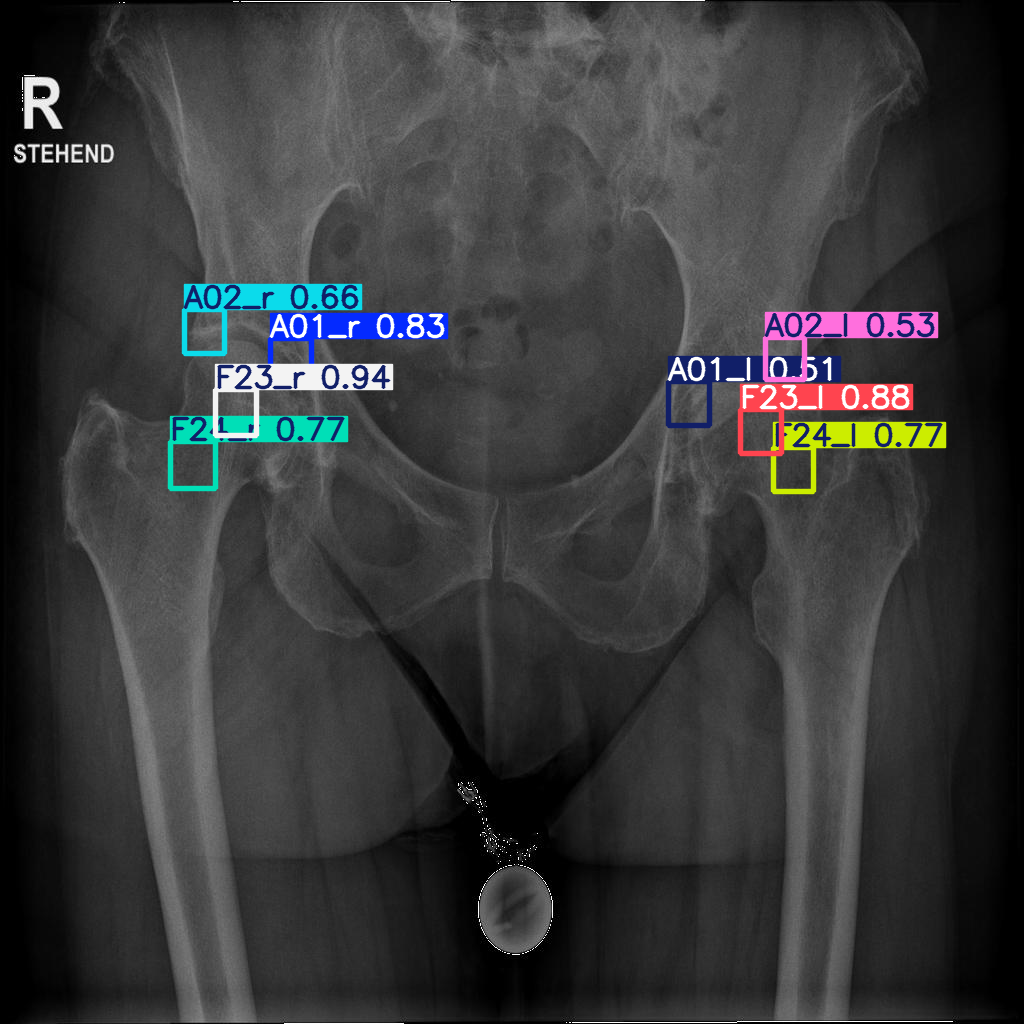

The mean and median accuracies are significantly better than that of the segmentation algorithm (Fig. 4, Fig. 5). The lowest median accuracy across all landmarks was 0.5.

Refer to caption

Figure 5: Successful identification of all landmarks in a test image.

Training resources for SAM involved a computer cluster with a dedicated L40 NVIDIA, 8 CPU cores per task, and 200 GB memory for 36 hours. Figure 4 shows a typical successful result of identification. Figure 8 givens an example of a ground truth and a predicted segmentation. Results for 15 test cases, landmarks: